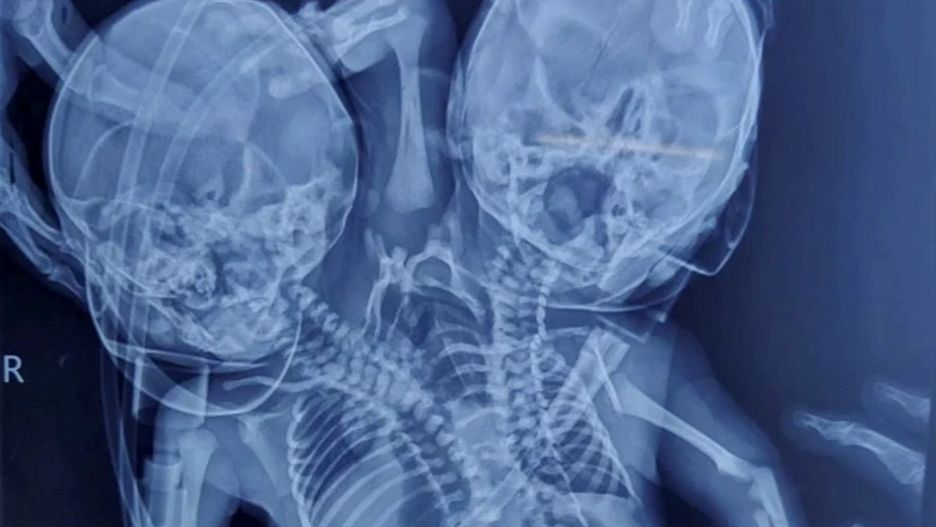

Shaheen Khan z Indii przez całą ciążę była przekonana, że urodzi dwoje zdrowych dzieci. Okazało się jednak, że na świat przyszły bliźnięta syjamskie. Mają jedno ciało, ale dwie głowy, dwa serca i trzy rączki. Nie wiadomo czy przeżyją.

Bliźnięta mają wspólny tors, dwie głowy, dwa serca i trzy rączki. Rodzice, po początkowym szoku, postanowili zapewnić dzieciom opiekę i wychować je najlepiej jak potrafią.

Bliźnięta pozostają pod stałą obserwacją lekarzy w specjalistycznym szpitalu w mieście Indore. Wciąż nie wiadomo czy przeżyją. Lekarze nie są także pewni czy mają do czynienia z bliźniętami, czy jednym dzieckiem. Ta kwestia może się wyjaśnić w najbliższym czasie.

Bliźnięta urodziły się z zaburzeniem zwanym policefalią. Organizm ma wówczas jedno ciało, ale więcej niż jedną głowę. Głowy zazwyczaj mogą w równomiernym stopniu dysponować ciałem. Najsłynniejsze bliźniaczki z policefalią to Abigail i Brittany Hensel z USA. Kobiety są uznawane za oddzielne osoby, a każda z nich ma swoją część ciała, którą kontroluje.

Zdarzają się jednak przypadki kiedy bliźnięta z tym schorzeniem są uznawane za jedną osobę. Dzieje się tak wtedy gdy głowa jest pasożytnicza i nie spełnia żadnych funkcji lub w momencie gdy wszystkie części ciała prócz głów są wspólne.